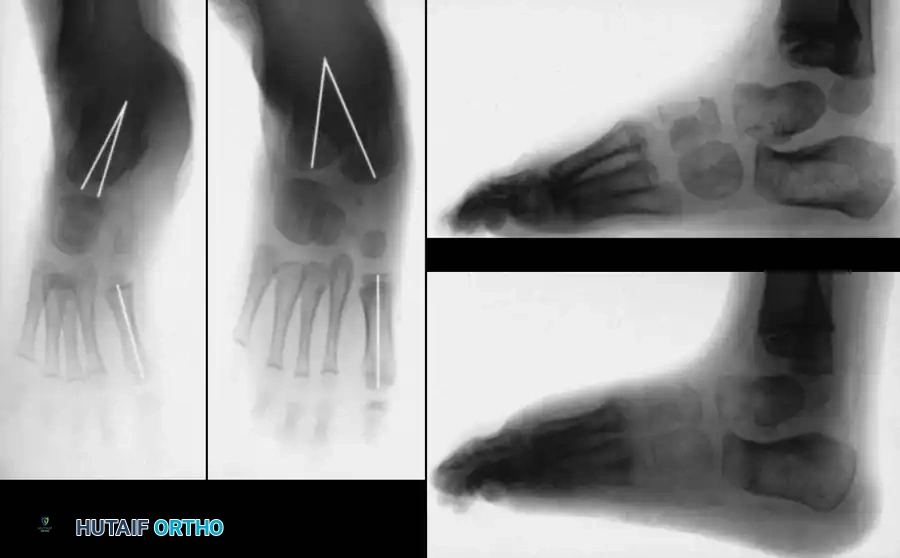

In older children (typically >4 years) where adaptive bony changes have occurred, soft-tissue releases alone are insufficient. Bony osteotomies are required to correct the lateral column overgrowth and medial column shortening.

McHale Procedure (Medial Cuneiform Opening Wedge and Cuboid Closing Wedge)

For residual "bean-shaped" foot deformities characterized by severe midfoot adductus:

1. Lateral Incision: A closing wedge osteotomy of the cuboid is performed to shorten the lateral column.

2. Medial Incision: An opening wedge osteotomy of the medial cuneiform is performed.

3. Graft Transfer: The bony wedge excised from the cuboid is meticulously shaped and impacted into the medial cuneiform osteotomy to lengthen the medial column.

4. Fixation: Both osteotomies are stabilized with K-wires.

Image

Fig. 20: Osteotomies of the medial cuneiform and cuboid for correction of residual deformity. (A) Lateral and medial incisions. (B) Removal of dorsolateral wedge from the cuboid. (C) Placement of the wedge into the opening osteotomy of the medial cuneiform.

Fig. 21: Radiographic appearance post-midfoot osteotomies, demonstrating restoration of the straight lateral border of the foot.